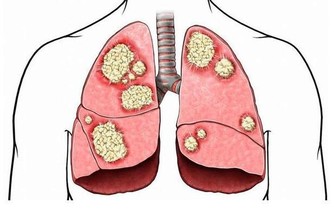

我們的肝臟不僅僅是解毒和代謝的器官

首先肝臟是分泌膽汁的一個器官,如果肝臟出現問題時,那麼膽汁的分泌就會受到或多或少的影響